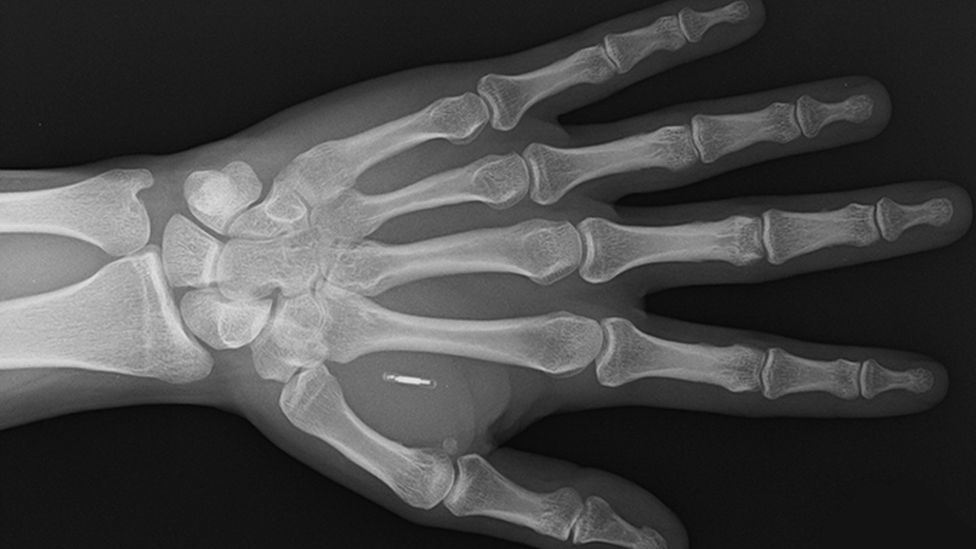

He can pay with his hand because he got a contactless payment microchip implanted under his skin in 2019.

A tiny microchip and an antenna are enclosed in a biopolymer - a naturally derived material comparable to plastic - in Walletmor's chip, which weighs less than a gram and is about the size of a grain of rice.